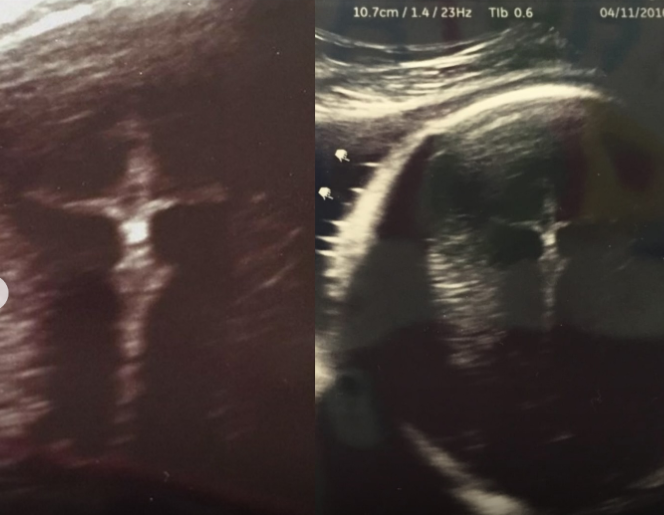

Ishusho ya Yesu ari ku Musaraba yagaragaye mu nda y'umubyeyi utwite

Ibinyamakuru birimo Cross Culcture na Faith on Christ, mu mpera za Kanama no mu ntangiriro za Nzeri 2025 byongeye gukwirakwiza inkuru nziza y’ibyabaye mu mwaka wa 2018, aho ishusho ya Yesu ari ku Musaraba yagaragaye mu nda y’umubyeyi wari utwite, akagira ikibazo cy’uburwayi cyasabye ko anyuzwa mu cyuma

Mu mwaka wa 2016, umugore utwite wo muri leta ya Indiana, muri Leta Zunze Ubumwe za Amerika, yagiye kwa muganga bisanzwe, agiye gukorerwa isuzuma ryifashisha ultrasound kugira ngo barebe uko umwana uri mu nda ameze, babonamo n’ishusho ya Yesu ku Musaraba.

Byari isuzuma risanzwe, rikorwa n’abagore batwite bose, ariko icyo gihe hari ikintu kidasanzwe cyabaye. Ibikoresho bya siyansi byasohoye ishusho y’inda ye, ya mashusho y’umukara n’umweru (black and white), asanzwe agaragara kuri ecran.

Mu ishusho, habonekagamo umwana uri gukura. Ariko si we gusa wabonetse. Mu gicucu cy’iyo shusho, mu bice bitagaragara neza, hari igisa n’isura y’umuntu ufite amaboko arambuye nk’ari ku Musaraba.

Abari bamufashe amashusho baratunguwe. Abavandimwe n’inshuti babibonye basakuje bavuga bati: “Reba neza! Aha hari igishushanyo cy’Umusaraba! Ni umuntu umeze nka Yesu!” Benshi bahise babona ishusho isobanura ikintu gikomeye kurusha igikoresho cya siyansi: ishusho y’umukiza uri hafi y’umwana utaravuka.

Aya ni amashusho ya nyayo yagaragaye mu byuma byo kwa muganga, Yesu agaragara ku Musaraba mu nda y’umubyeyi utwite, ari inyuma y’umwana.